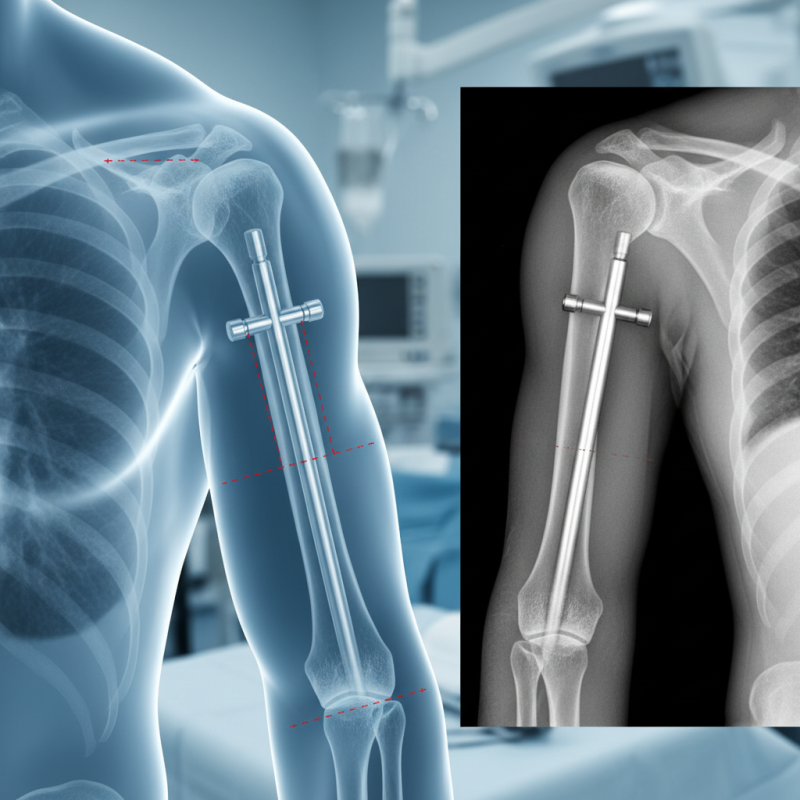

The Humeral Interlocking Nail is an innovative solution in orthopedic surgery. This device is designed to stabilize complex fractures of the humerus, which is crucial for recovery. Surgeons use it to align and hold fractured bone segments securely.

Humeral interlocking nails are specialized medical devices. They are used to treat fractures in the upper arm bone, known as the humerus. This nail provides robust internal support during healing. Surgeons insert it through the bone, providing stability.

Humeral interlocking nails are increasingly employed in orthopedic surgery. Their primary purpose is to stabilize fractured humeral shafts. Research shows that these devices can significantly reduce healing time. A study indicated a 25% faster union rate when using interlocking nails versus traditional plating methods.

Indications for using humeral interlocking nails include complex fractures, non-union cases, and certain types of osteotomies. Surgeons often opt for this method when there is a risk of soft tissue compromise. The nails provide superior mechanical stability while allowing for early mobilization. A report from the Journal of Orthopedic Trauma highlights that up to 70% of patients benefit from this approach in active lifestyles.

The surgical procedure for inserting a humeral interlocking nail is an intricate process. Surgeons begin with a small incision near the upper arm. Careful planning is essential to ensure the nail aligns correctly with the humerus. The nail is designed to stabilize fractures, allowing for proper healing. Use of imaging techniques, like X-rays, assists in placing the nail effectively.

Once the incision is made, the surgeon drills a hole into the bone. This step requires precision. The humeral interlocking nail is then inserted through this hole. Next, locking screws are placed to secure the nail. This stabilizes the bone during the healing phase. Surgeons must be cautious of surrounding nerves and blood vessels during the operation.